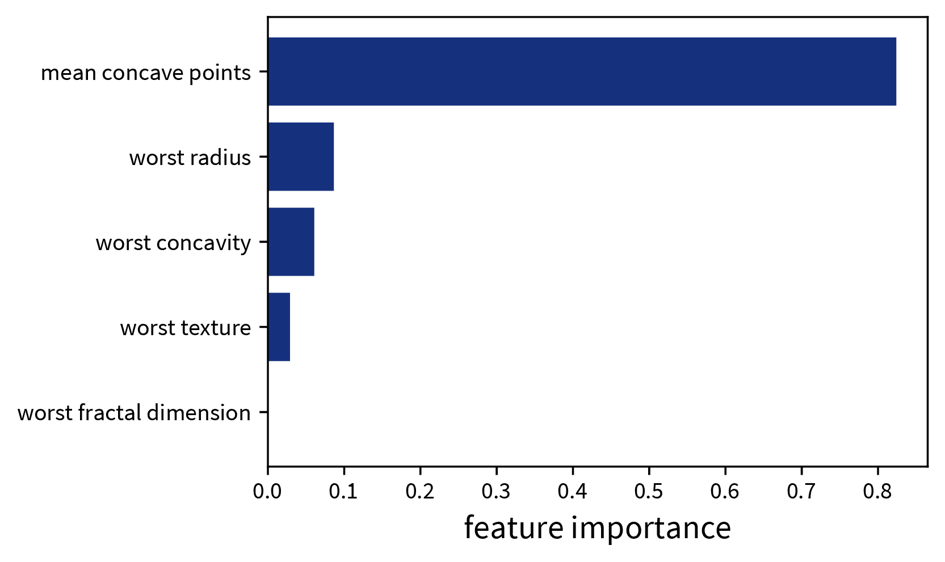

sklearn. The decision tree has its root at the top (where we start when predicting for a new sample) and the leaves (i.e., those nodes that don’t branch off anymore) at the bottom (where we stop and make the final prediction). Each node in the tree shows in the first line the variable based on which the next split is made incl. the threshold value (except for leaf nodes), then the current Gini impurity (i.e., how homogeneous the labels of all the samples that ended up in this node are; this is what the decision tree internally optimizes, i.e., notice how the value gets smaller on at least one side after a split), then the fraction of samples that ended up in this node, and the distribution of samples for the different classes (for a classification problem), as well as the label that would be predicted for a sample at this point. So when making a prediction for a new sample with a decision tree, we start at the root node of the tree and then follow the branches down depending on the sample’s feature values until we reach a leaf node and would then know exactly based on which feature thresholds the prediction for the sample was made.Global interpretation: a trained decision tree or random forest has an attribute feature_importances_, which indicates how much each feature contributed to reducing the (Gini) impurity. This is related to the position of the feature in the tree and how many samples pass through the respective node.

feature_importances_ attribute of the decision tree shown above. When we’re using a random forest instead of a single decision tree, it would be impractical to plot all of the individual trees contained in the forest to explain individual predictions, but a random forest at least also has the feature_importances_ attribute to examine the global importance of the different features.Explaining Linear Models (& Neural Networks)